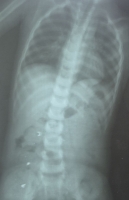

"Семья отправилась в Хвалынскую больницу, где ребенку был выполнен рентгеновский снимок, который показал наличие инородного тела в желудке. Юного пациента перенаправили в БГКБ. Контрольный снимок отчетливо показал, что, во-первых, инородное тело состоит из трех частей, а во-вторых, что они находятся уже не в желудке, а распределились по кишечнику", - рассказали врачи.